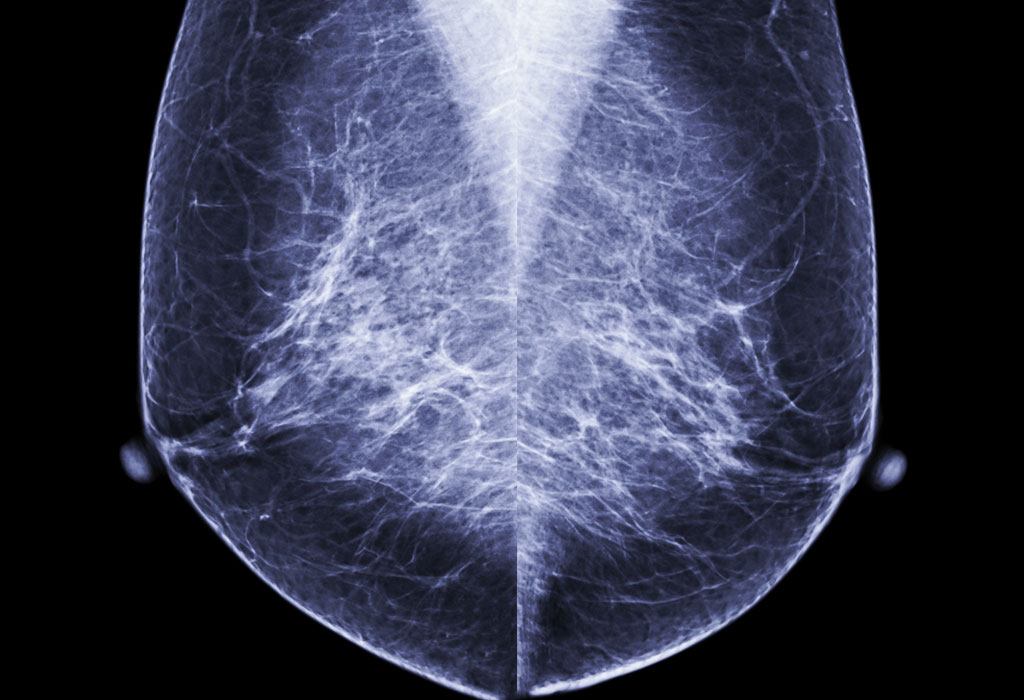

„Liječnici Intermountain Healthcare LSD Hospital iz Salt Lake Citya najavili su u utorak nove smjernice (protokol) za mamografiju kao odgovor na iznenađujuću novu nuspojavu cjepiva COVID-19. Kažu da će žene koje su nedavno primile COVID-19 cjepivo možda morati preurediti godišnji mamografski pregled. (1)

U posljednja četiri tjedna liječnici su vidjeli natečene limfne čvorove na screening mamogramima žena koje su nedavno cijepljene. “Kad god ih vidimo na uobičajenom mamografskom pregledu, zovemo te pacijente natrag, jer to može značiti ili metastatski rak dojke koji putuje u limfne čvorove ili limfom ili leukemiju.” Iako je upala uobičajeni odgovor tijela na cjepivo, dr. Parkinson kaže da je iznenađujuće koliko su natečenih limfnih čvorova vidjeli. (2)

“S cjepivom Moderna to je oko 11 % nakon prve doze i 16 % nakon druge doze. Vjerujemo da je usporedivo i s cjepivom Pfizer.” Kao odgovor, bolnica Intermountain Healthcare LSD Hospital izdala je nove smjernice (protokole) u skladu s Društvom za snimanje dojki.

Žene bi trebale napraviti mamografiju prije prve doze cjepiva, te četiri tjedna nakon druge doze cjepiva. “Ne želimo da ovi pacijenti dobiju lažno pozitivan signal da imaju ovakavu sumnju”, rekao je dr. Parkinson.

Ako postoje zabrinjavajući simptomi, poput sumnjive kvržice, dr. Parkinson kaže da ne odgađate mamografski pregled. “Rak dojke ubije žene između 40 i 50 000 godišnje. Mnoge od tih smrti su nepotrebne ”, rekao je Parkinson. “Znam da su mamografski pregledi jedini test koji se pokazao učinkovitim tijekom posljednjih 30 do 40 godina kako bi se smanjila stopa smrtnosti od raka dojke.”